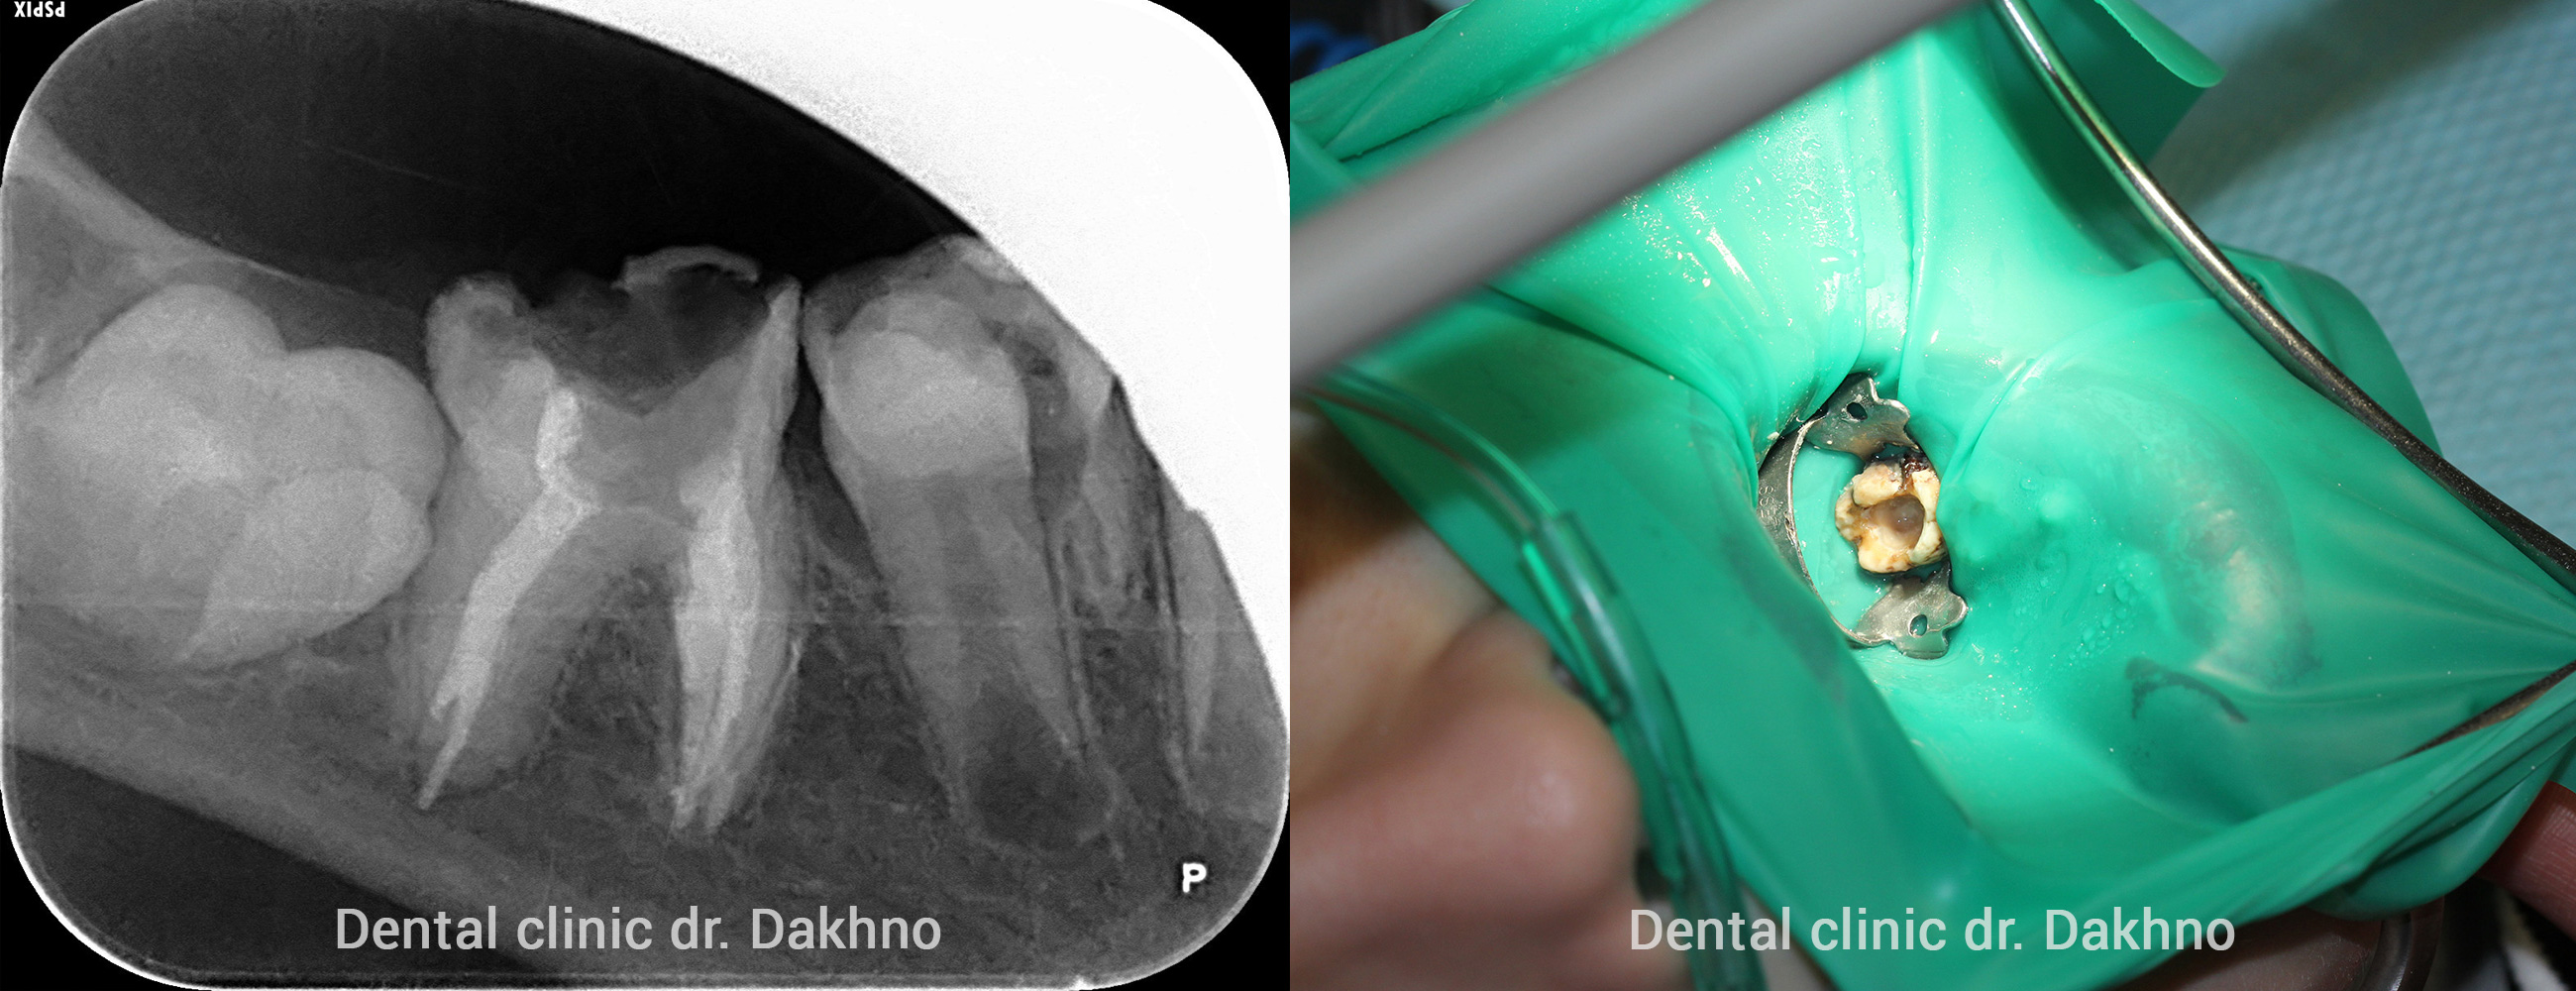

Стоматологічний діагноз: гіпогенезія верхньощелепних синусів. Двосторонній парез лицьового нерва. Рвотний рефлекс. Множинні дентіклі, як результат дентінодісплазіі. Системна гіпоплазія емалі. Множинний циркулярний карієс, в перших молярах постійних зубів ускладнений хронічним пульпітом.

Виходячи з даних анамнезу, клінічної та рентгенологічної картини – необхідна повна санація порожнини рота і відновлення жувальної ефективності.

Беручи до уваги соматичний статус і виражений блювотний рефлекс, прийнято рішення провести першим етапом лікування кореневих каналів (доктор Лілік Сергій Васильович) під загальною анестезією (медикаментозний сон) в супроводі анестезіолога Стецюк Олени Володимирівни.

Етапи лікування карієсу